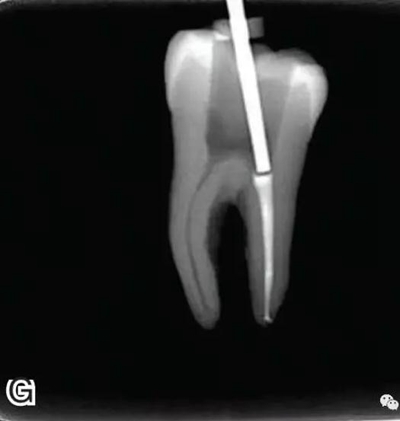

3、試尖

選擇非標(biāo)準(zhǔn)牙膠尖(如0.04、0.06 錐度牙膠尖)作為主尖,型號一般與根管預(yù)備最大號的器械型號一致,能到達(dá)距根尖0.5~1 mm 處,主尖尖段與根管壁緊密接觸。拍試尖X 線片進(jìn)行確認(rèn)(圖3)。

圖3 試尖,A.試主尖 B.拍試尖X片